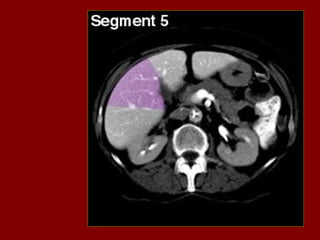

INCISÃO SOBRA AVEIA HEPÁTICA DIREITA

INCISÃO SOBRE AVEIA HEPÁTICA MÉDIA.

INCISÃO SOBRE AVEIA HEPÁTICA ESQUERDA.